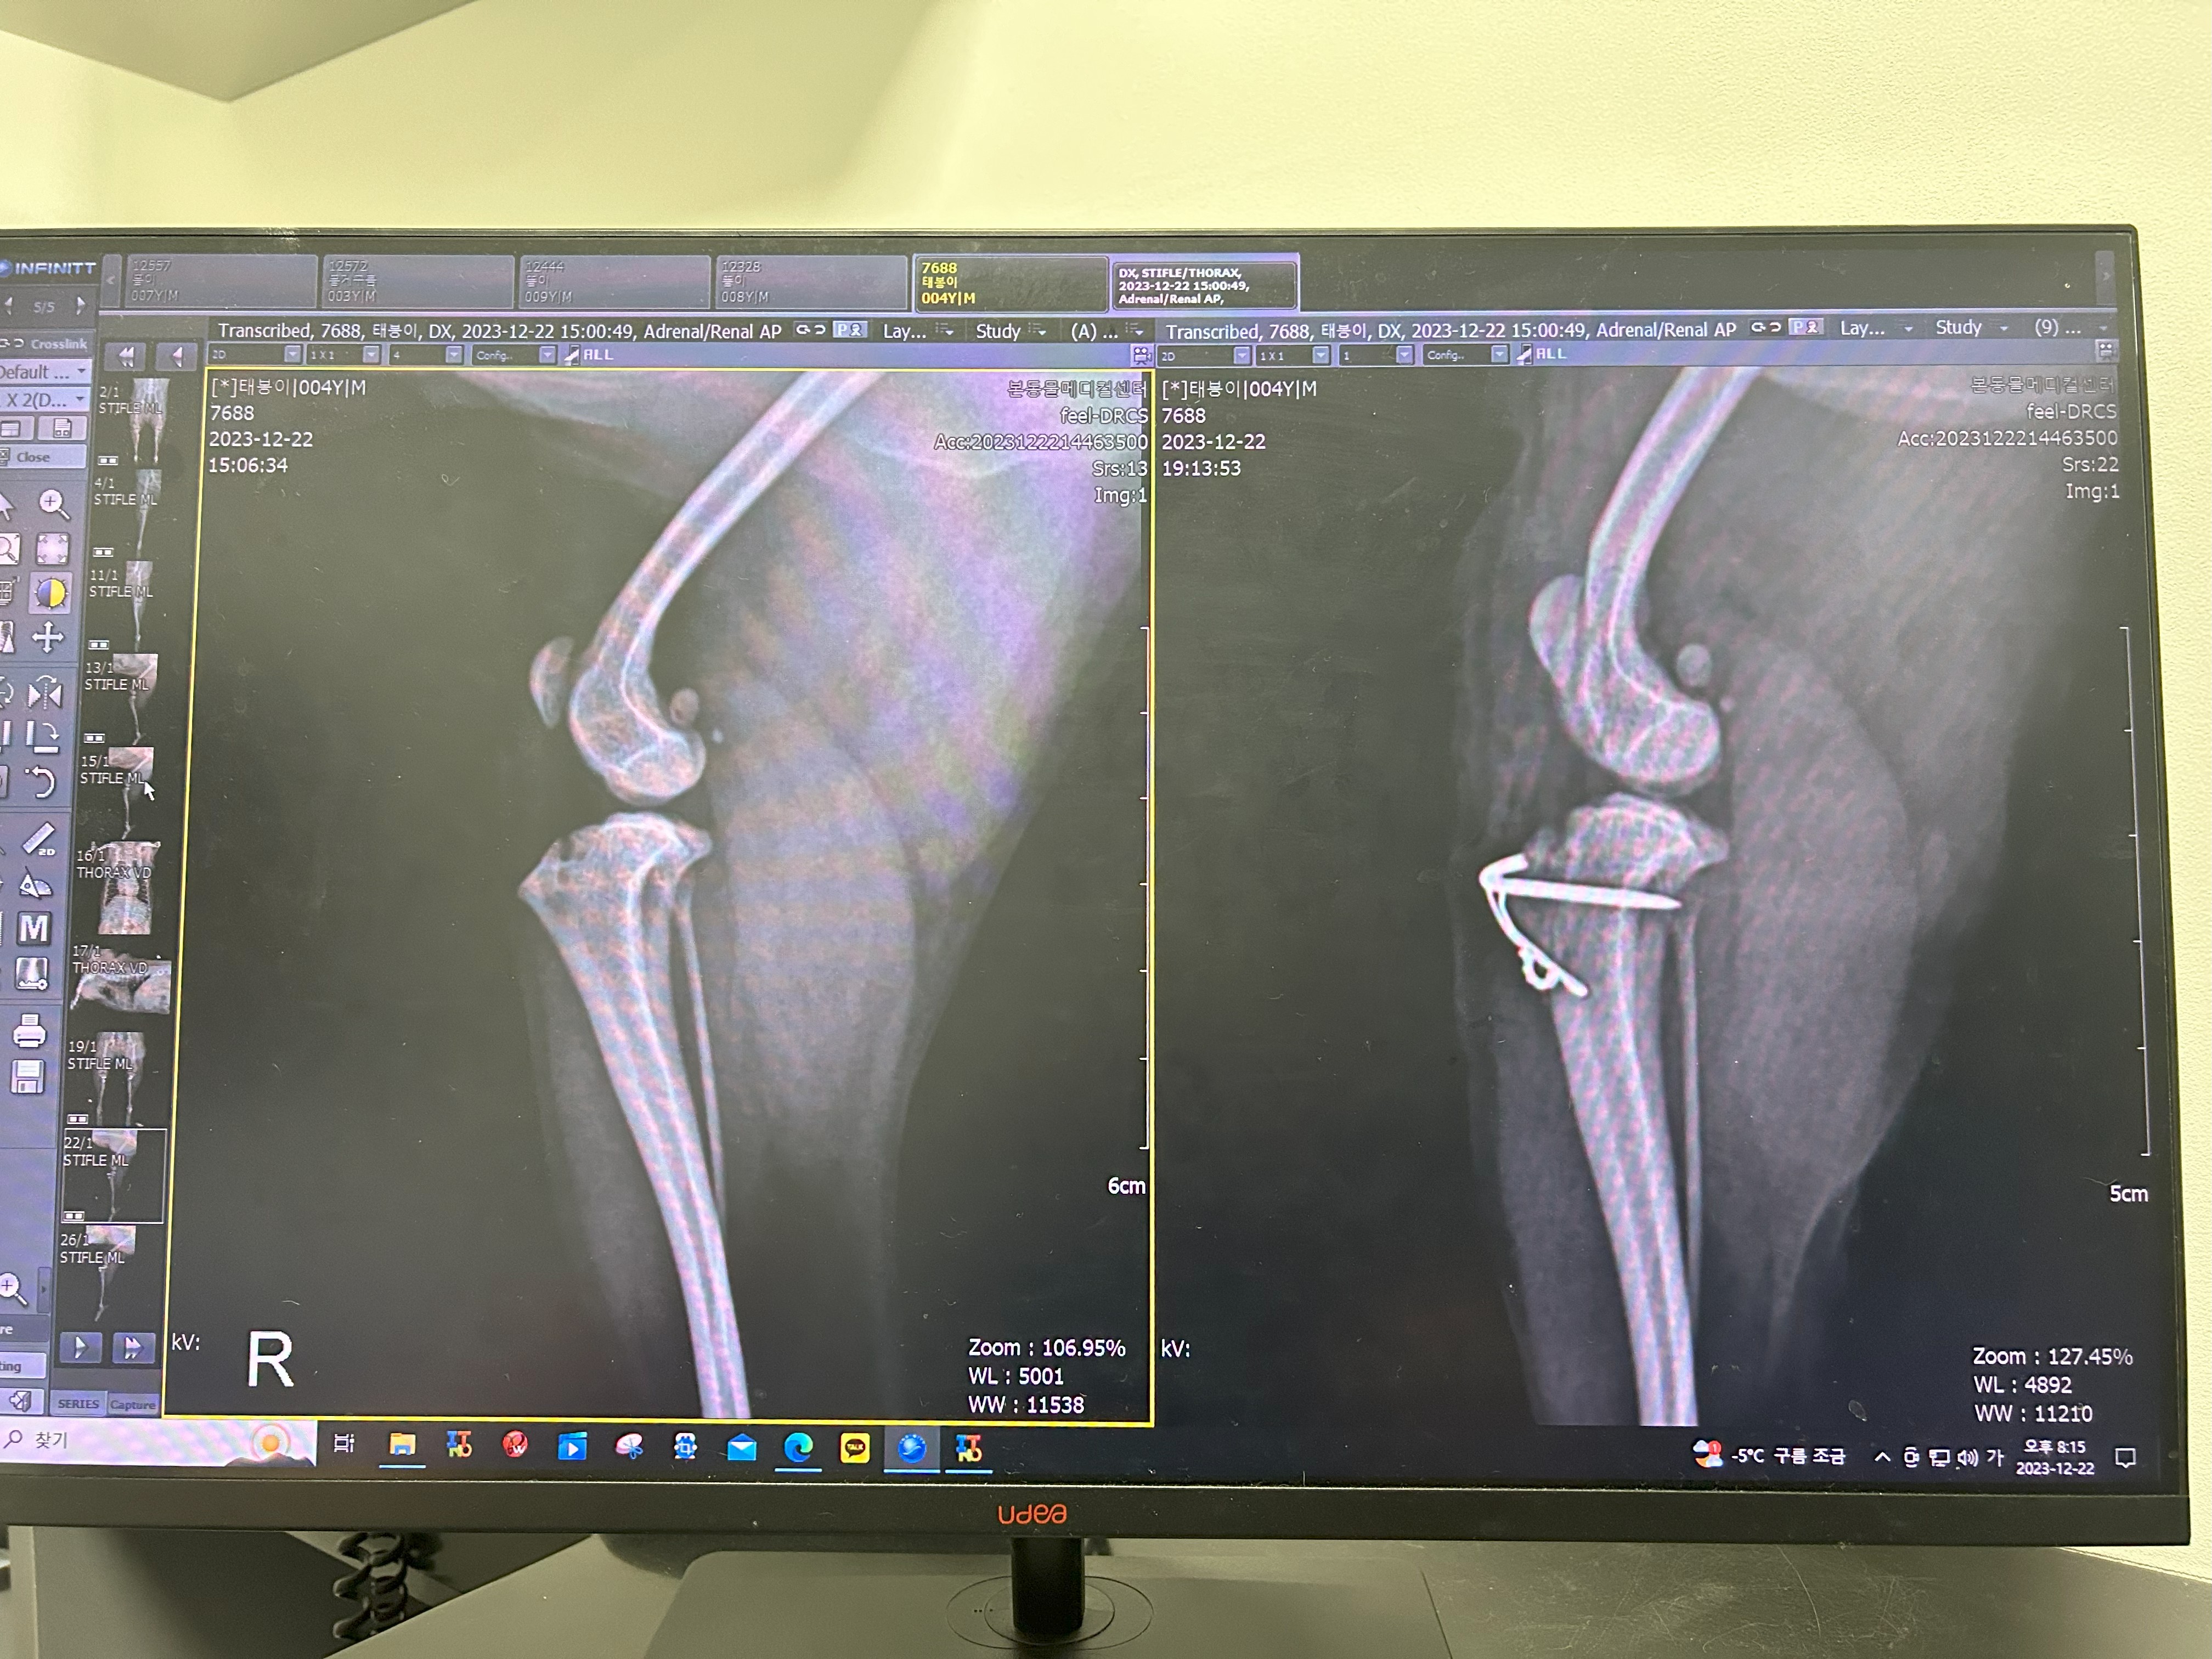

태봉이가 하게 된 강아지 슬개골탈구 수술은 세 가지를 한다고 했어요

제가 전문적인 용어는 잘 몰라서 저의 수준으로 설명을 하자면

소형견들은 무릎뼈를 받쳐주는 뼈의 골이 매우 얕거나 거의 평평해서 경우에 따라 슬개골이 빠지는 경우가 많은데

그 뼈의 홈을 깎아내서 인의적으로 골을 내줘야 합니다.

그래서 그 홈을 깎아내는 수술을 해야 하고

거기에 슬개골이 빠지면서 제자리에 위치하지 못한 슬개골을 제자리에 위치하게 하는 수술,

그리고 와이어로 슬개골을 고정하는 것까지 이렇게 세 가지를 진행했어요